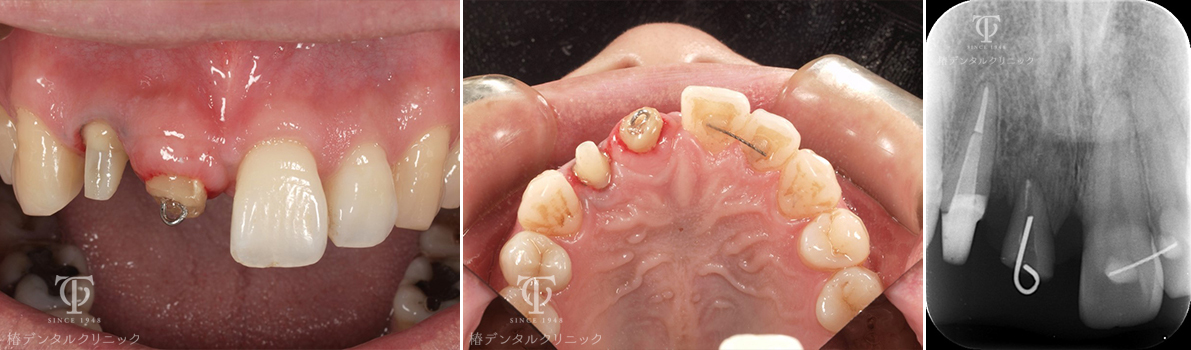

Case05

歯根破折の為、前歯が位置異常をおこしていました。

残った歯を部分矯正治療で引っ張り硬組織・軟組織を再生させました。

術前

術後

- 症状

- 前歯を綺麗にしたい

- 治療期間

- 約1年半

- 治療費用

- 部分矯正治療:330,000円×2

インプラント治療:473,000円

オールセラミッククラウン:165,000円

歯根破折をおこし前歯が位置異常をおこし綺麗にしたいということで来院されました。残った破折歯を部分矯正治療に利用して骨造成を回避しました。

【リスク・副作用】

インプラント治療後、痛みや違和感、出血、腫れなどが出る事があります。喫煙者、糖尿病などの方の場合、歯が生着しない場合があります。